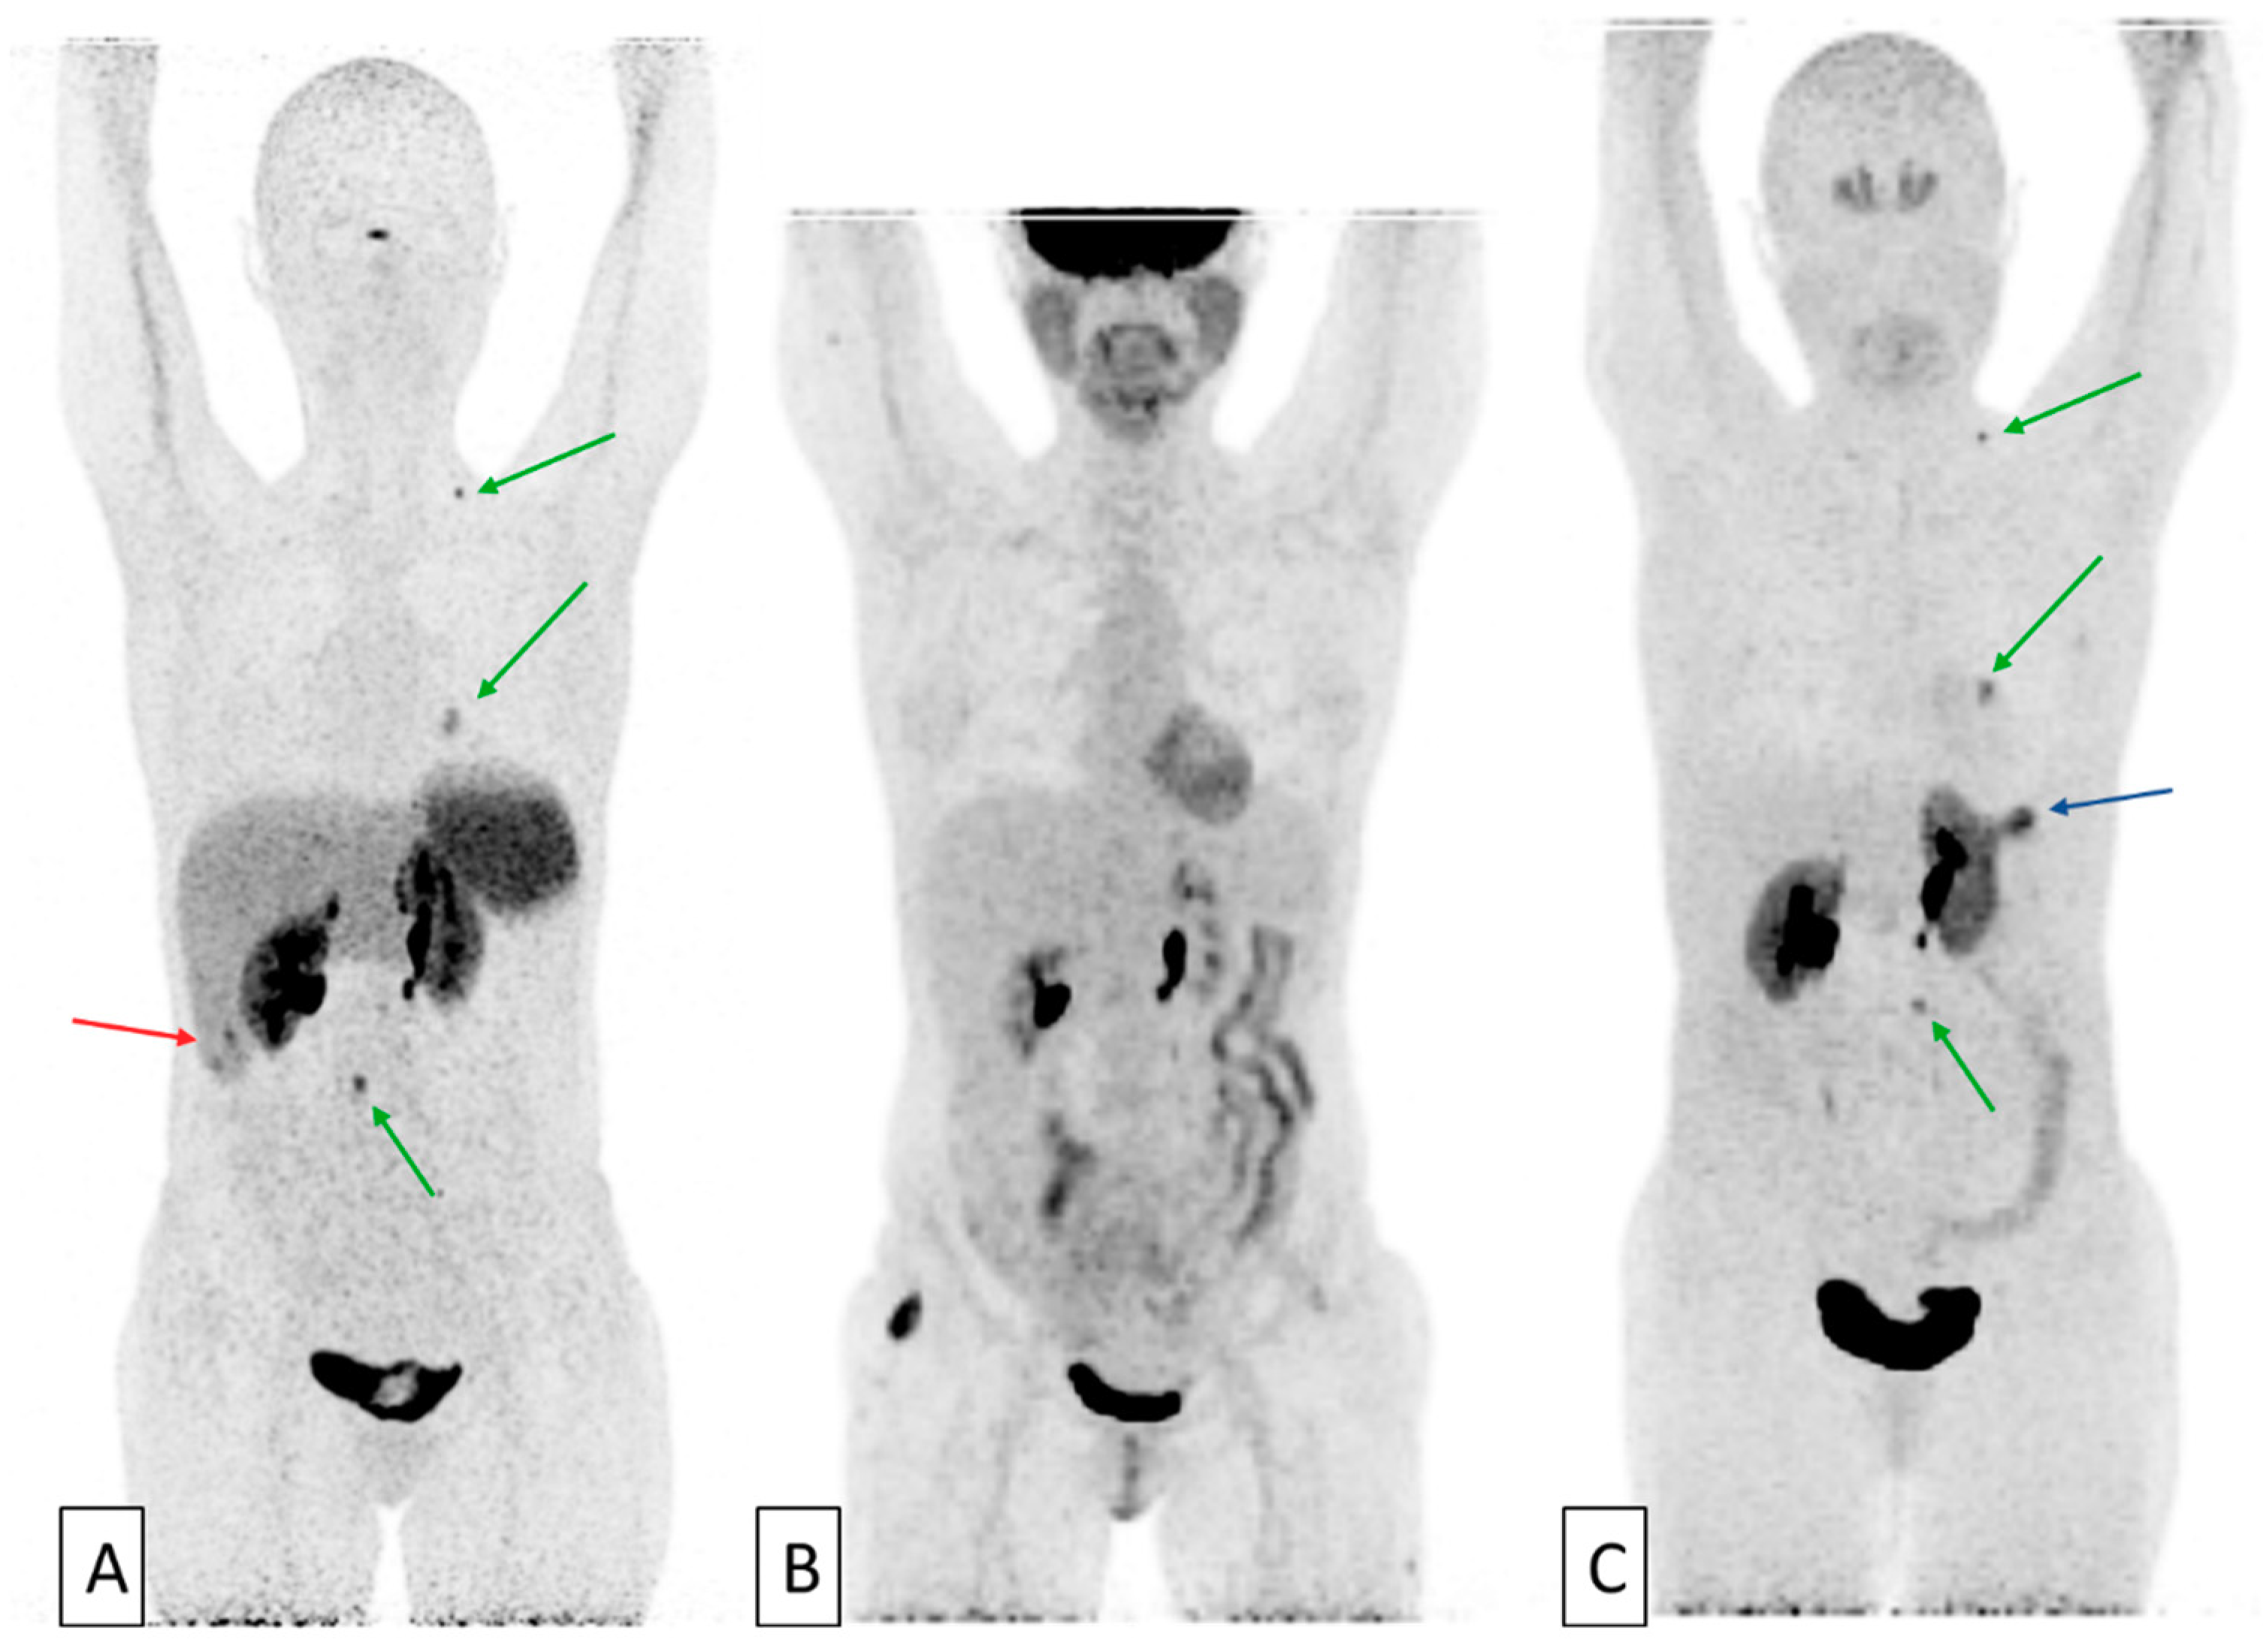

- Chan, D.L.; Pavlakis, N.; Schembri, G.P.; Bernard, E.J.; Hsiao, E.; Hayes, A.; Barnes, T.; Diakos, C.; Khasraw, M.; Samra, J.; et al. Dual Somatostatin Receptor/FDG PET/CT Imaging in Metastatic Neuroendocrine Tumours: Proposal for a Novel Grading Scheme with Prognostic Significance. Theranostics 2017, 7, 1149–1158. [Google Scholar] [CrossRef] [PubMed]

- Zhang, P.; Yu, J.; Li, J.; Shen, L.; Li, N.; Zhu, H.; Zhai, S.; Zhang, Y.; Yang, Z.; Lu, M. Clinical and Prognostic Value of PET/CT Imaging with Combination of 68Ga-DOTATATE and 18F-FDG in Gastroenteropancreatic Neuroendocrine Neoplasms. Contrast Media Mol. Imaging 2018, 2018, 2340389. [Google Scholar] [CrossRef]

- Hindié, E. The NETPET Score: Combining FDG and Somatostatin Receptor Imaging for Optimal Management of Patients with Metastatic Well-Differentiated Neuroendocrine Tumors. Theranostics 2017, 7, 1159–1163. [Google Scholar] [CrossRef] [PubMed]